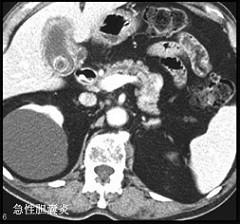

问题 有关急性胆囊炎哪项是错误 ( )

选项 A、一般无寒战 B、黄疸出现早而明显 C、右上腹可有压痛、肌紧张 D、胆囊区深吸气时有触痛反应 E、有时可扪及有触痛的肿大胆囊

答案 B